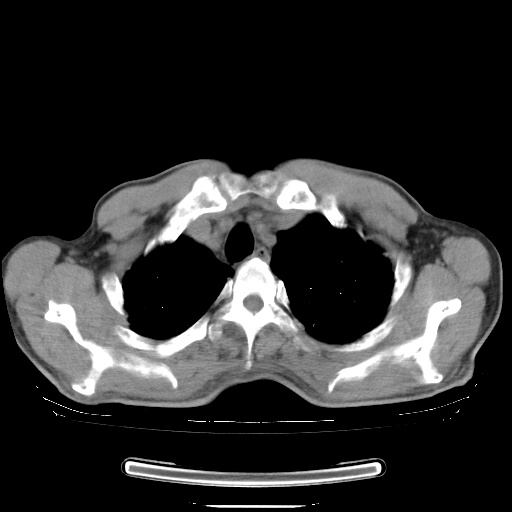

男性患者,63岁。右侧胸背部疼痛2月,加重一周。

还有纵隔多处肿大淋巴结及肋骨的改变、两肺多发结节灶。

考虑右中心型肺癌并右下肺不张,肺及纵隔,左肋骨转移。

右肺下叶中心性肺癌并纵隔淋巴结转移,左侧肋骨转移。双肺上叶继发性结核表现。

1)右肺下叶中心性肺癌并纵隔淋巴结转移,两肺转移,左侧肋骨转移。2)双肺上叶继发性结核。

右肺下叶中心性肺癌并纵隔淋巴结及两肺、左侧肋骨转移。双肺上叶继发性结核表现。